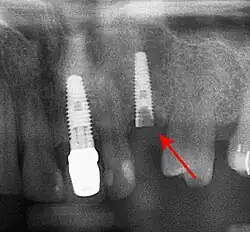

Die 5-Jahres-Überlebensrate von Zahnimplantaten liegt seit Einführung der Titanimplantate sehr hoch bei 96,8 %.[1] Diese Implantate osseointegrieren und gehen damit eine ankylotische Verbindung mit dem umgebenden Kieferknochen ein. In seltenen Fällen ist jedoch die Entfernung eines Implantats, beispielsweise bei einer fortgeschrittenen Periimplantitis, angezeigt. Wenn dabei der Knochenabbau nur partiell erfolgt ist, muss der noch osseointegrierte Teil gelöst werden. Bei Vorliegen eines Lockerungsgrades I (gerade tast- und spürbare, kaum sichtbare horizontale Beweglichkeit des Implantats) eines zuvor osseointegrierten Implantates konnte in einem diesbezüglichen Review die Explantation nicht umgangen werden.[2] Die Explantation ist auch indiziert bei Sondierungstiefen größer als 8 mm.[3]

Eine Explantation muss in manchen Sonderfällen vorgenommen werden, beispielsweise bei einer Irritation eines Nerven (insbesondere des Nervus mandibularis), bei Parästhesien, bei einer Neuralgie, bei einer Sinusitis maxillaris, bei Implantatfrakturen oder bei einem falsch platzierten Implantat. Bei Implantaten im vorbestrahlten Kiefer ist die Prognose mit einer Überlebensrate von 72 % nach fünf Jahren deutlich schlechter als für enossale Implantate im gesunden Knochen.[4]